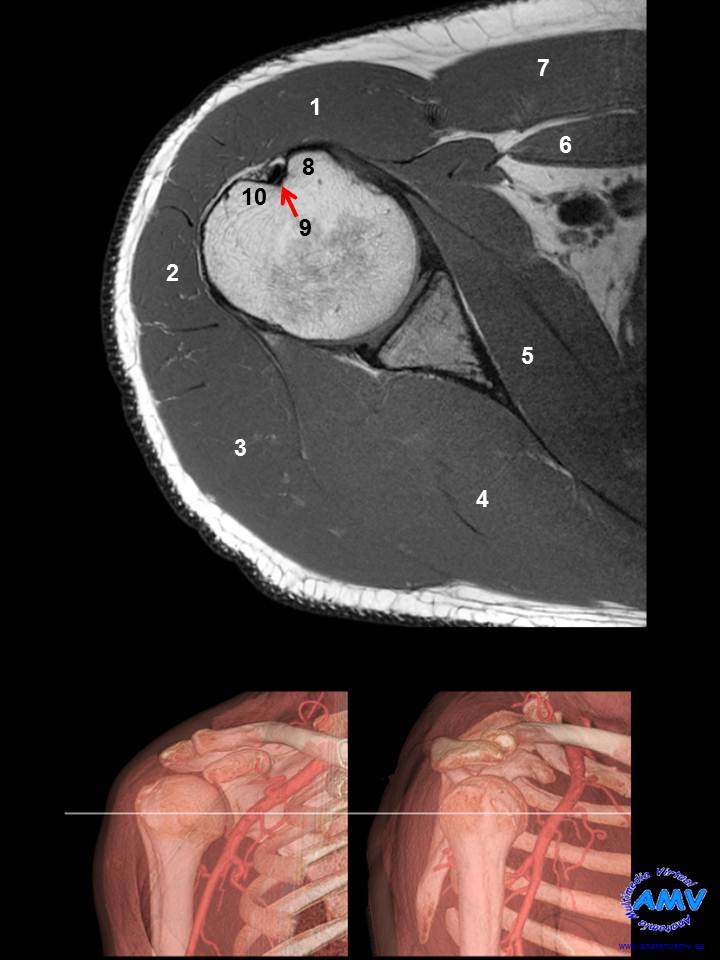

RMN Axial de Hombro

ms_rmn_01.jpgIndique que estructura se señala con el número correspondiente:

El nº 1 señala al músculo .

El nº 2 señala al músculo .

El nº 3 señala al músculo .

El nº 4 señala al músculo .

El nº 5 señala al músculo .

El nº 6 señala al músculo .

El nº 7 señala al músculo .

El nº 8 señala el relieve óseo .

El nº 9 señala el relieve óseo .

El nº 10 señala el relieve óseo .